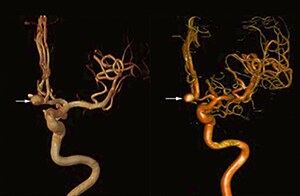

“The 3D TOF MR angiograms are obtained by using 3D T1- weighted FFE sequences (TR 35 ms, TE 7 ms, flip angle 20 degrees, field of view 250 × 190 × 108 mm, matrix 732 × 1024, four slabs, 180 slices of 0.8 mm thickness, acquisition time 8:56 minutes). On our Achieva 3.0T MRI system with an 8-channel head coil, 3D TOF is easy to use and the background signal suppression is very good. Maximum intensity projections (MIPs) and volume-rendered images are reconstructed from the data. We use a single-artery highlighting method to reduce arterial overlay. The method can also be used for carotids or other small intracranial vessels.”

“Advances in MR imaging, the high SNR and spatial resolution of 3.0T, increasing observer experience and improved postprocessing techniques have improved the capabilities of MRA over the last decade. We found that 3D TOF MRA provides excellent images for the visualization of small cerebral aneurysms which enables us to accurately diagnose, and this accuracy appears to be similar to that obtained with DSA according to data from a 2014 study," [2] Dr. Li says. “Aneurysm location can influence how easy it is recognized. Infundibula can mimic aneurysms, adding to the difficulty of interpretation. On MIP images, small aneurysms can also be easily misinterpreted when the aneurysm overlaps with the vessel. This is why in our method we are viewing the images from multiple angles.” “In the hundreds of patients with aneurysms that we scanned, we saw no significant differences in accuracy, sensitivity or specificity among the locations. [2] We think this is the result of technical advances in image acquisition and postprocessing algorithms.”